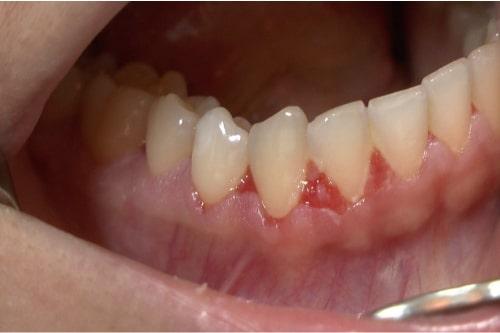

Stomatita dentară

Aceasta este o condiție obișnuită la purtătorii de proteză dentară. Apare ca o mucoasă înroșită dar fără dureri, sub proteză. Cele mai multe dintre cazuri sunt asociate cu specia Candida, și este cea mai obișnuită formă de candidoză orală. Tratamentul este cu medicamente antifungice și igienă bucală îmbunătățită, precum scoaterea protezei dentare în timpul somnului.